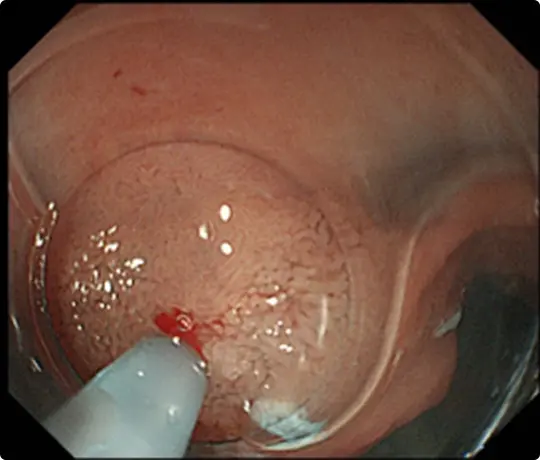

約3cmの大きな大腸ポリープです。

スネアでポリープの根元を縛り、電流を流して切除します(出血予防のためポリープの根元にクリップをうっています)。